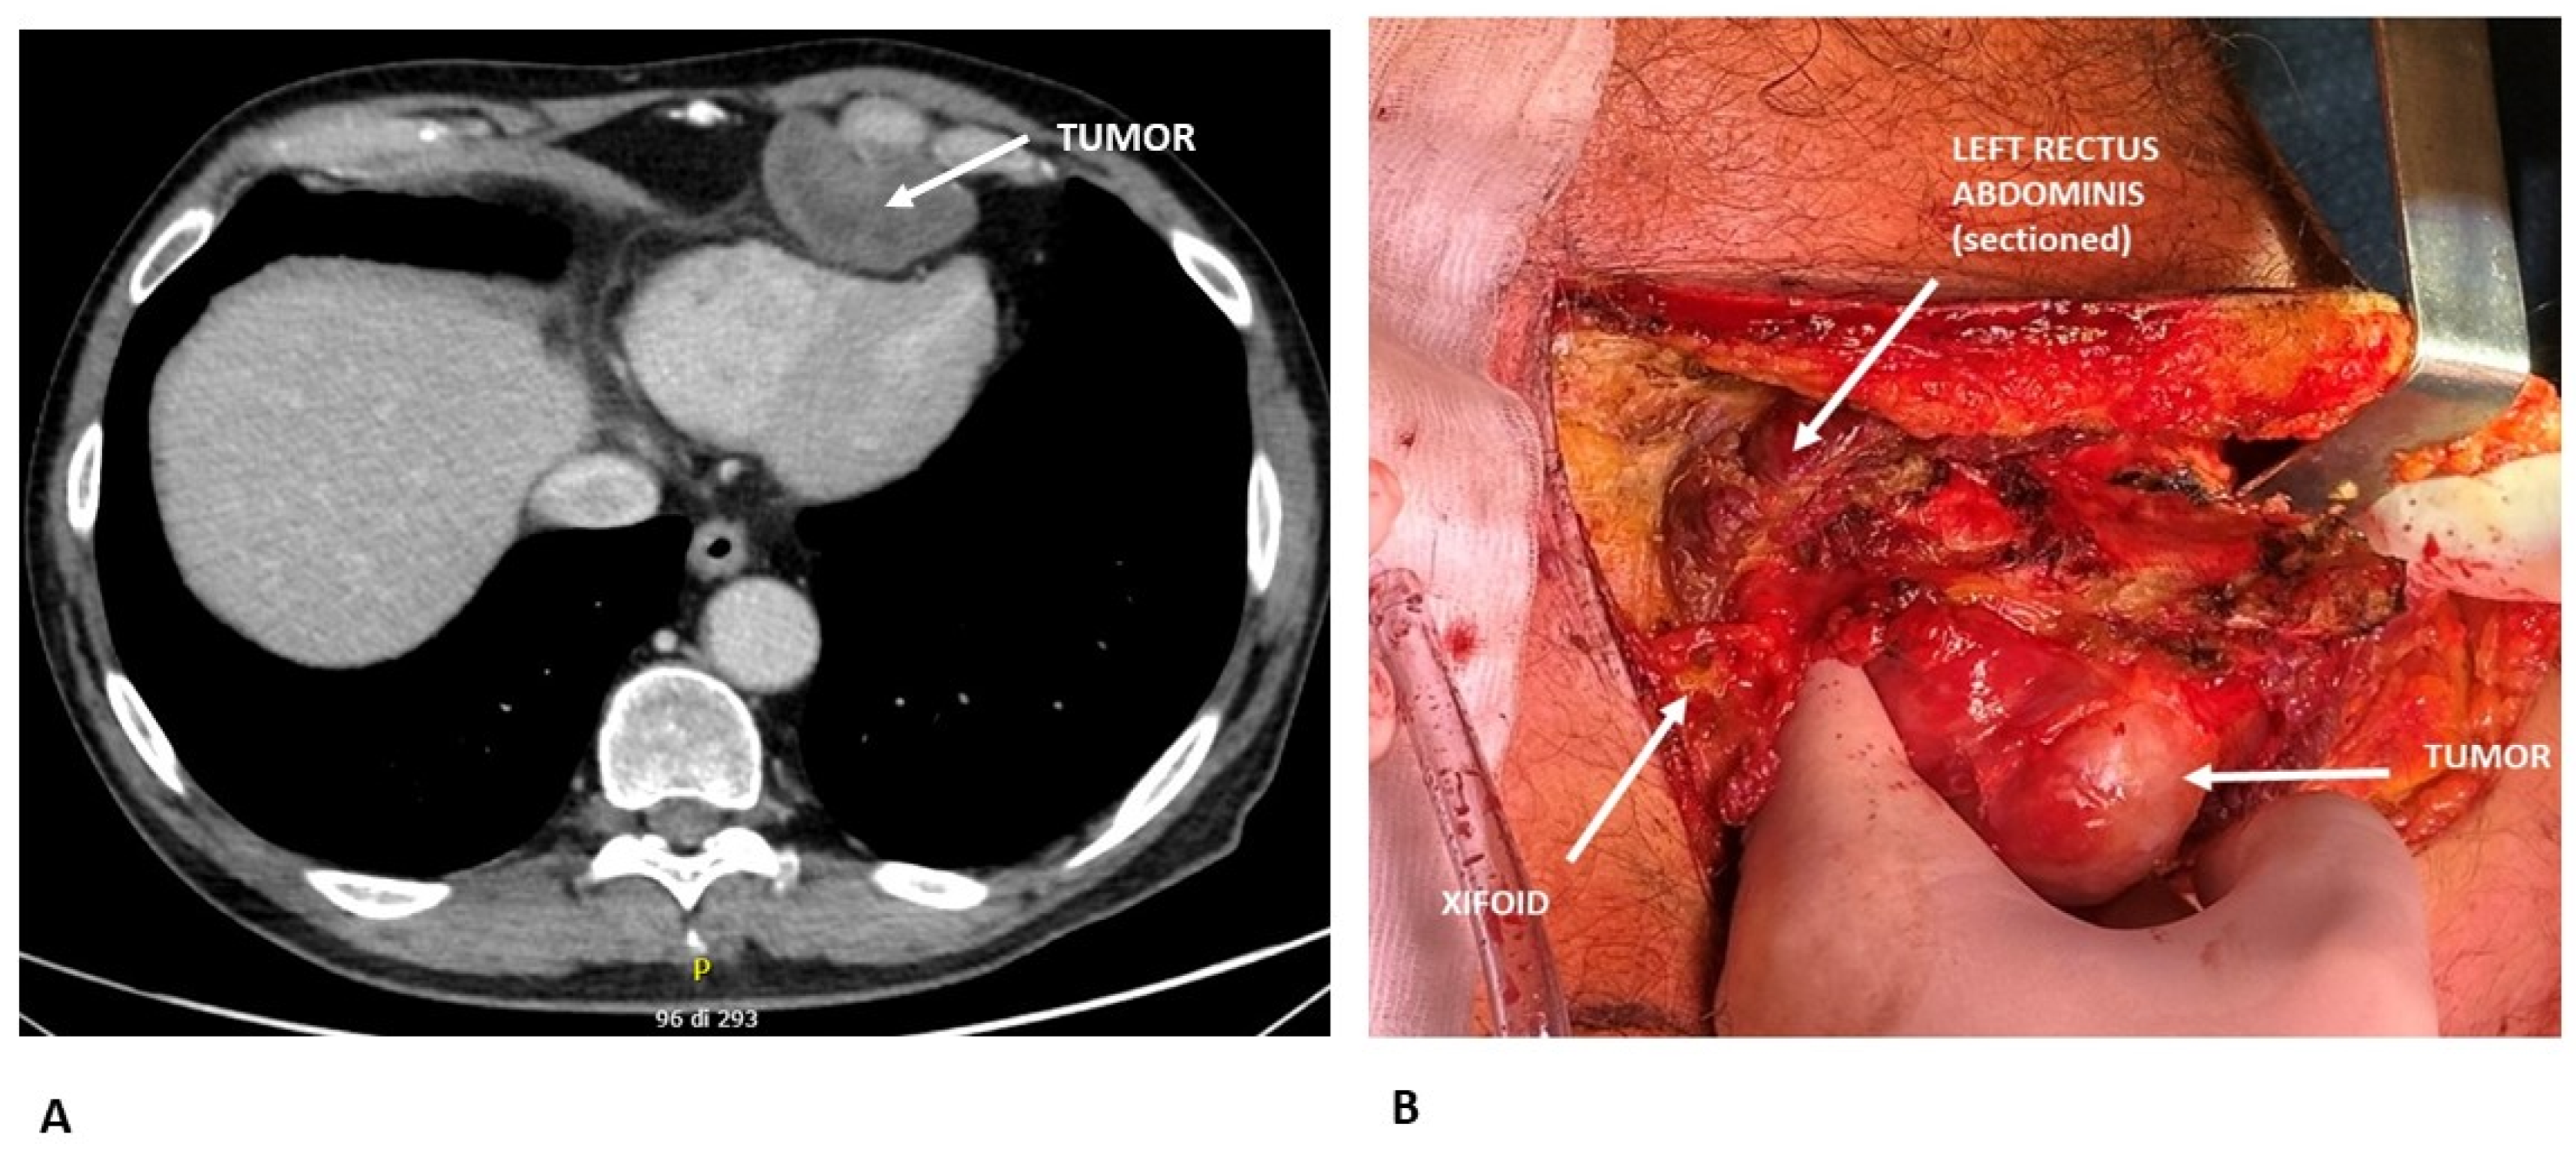

2.2. Primary Soft-Tissue Tumors

7. Discussion